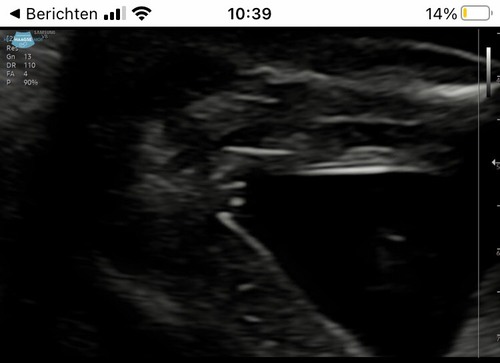

Ik heb nog een foto die hebben ze me via een link gestuurd.misschien is het daarop beter te zien